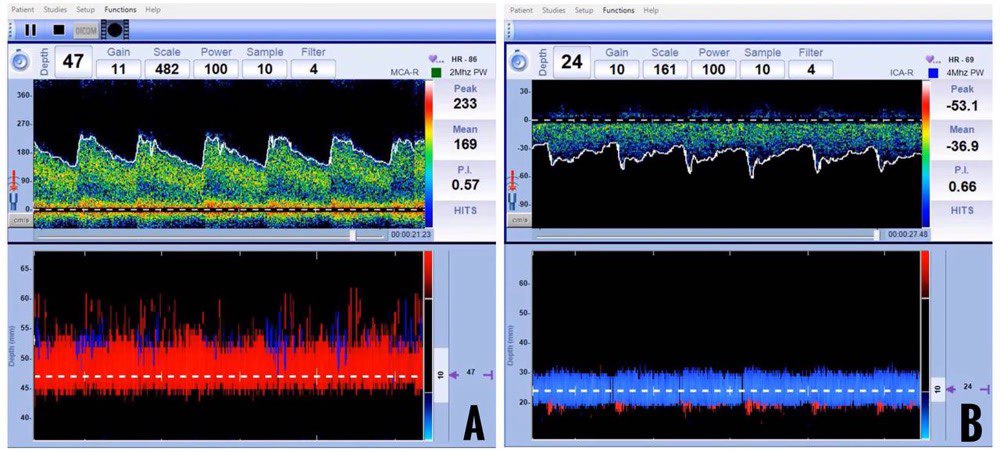

Once an ischemic stroke is identified in the window period and thrombolysis is performed, recanalization of the occluded artery is an expected outcome. Recanalization can be assessed by TCD by the reappearance of flow in the vessel or an improvement in the flow with or without reduction in the PI in the proximal segments of the vessel. Demchuk and colleagues have proposed thrombolysis in brain ischemia (TIBI) criteria for the TCD-based classification of MCA flows before and after thrombolysis (Table 7 and Figure 14).

| TIBI SCORE | FLOW STATUS IN MCA | TCD FINDINGS |

| 0 | Absent | Absence of regular pulsatile flow signals |

| 1 | Minimal |

|

| 2 | Blunted |

| 3 | Dampened |

| 4 | Stenotic |

| 5 | Normal |

EDV = end diastolic velocity, MFV = mean flow velocity, P = pulsatility index, TIBI Score = thrombolysis in brain ischemia score

Figure 14: Thrombolysis in brain ischemia (TIBI) score [Image adapted from Kargiotis et al.]25